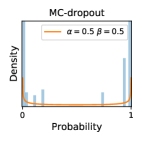

To model how different classifiers will respond to a given input , we assume that the prediction from classifier is sampled from a beta distribution that is characterized by two parameters by and . We further assume that is fixed to the same constant value for all ’s. Under this assumption, each input can be described by ( can be calculated since is fixed), easing further analysis. The Severity Level (SL) of the case represented by image can be characterized by the parameter . The larger the value of , the more severe the case of is. When and are close, the case is ambiguous as the distribution shifts towards being symmetric (i.e. signifying much disagreement among classifiers) rather than being one-sided (i.e. consensus among classifiers that is negative or positive). We provide a set of examples in Figure 2 and also Figure S.8 in the supplementary materials showing how the beta distribution can be used to capture diverse predictions given by an ensemble learner.

We conducted a case study on diagnosing diabetic retinopathy with ensembles of DL models. For benchmarking the performance of our ensemble-based solutions under the scheme described in Sec.3.3, we used two popular collections of diabetic retinopathy image data, the Kaggle Diabetic Retinopathy dataset [22] (hereafter referred to as “Kaggle-DR”) and the Messidor-2 dataset [23], each respectively consisting of and high resolution images. Diabetic retinopathy is graded into five SLs, as displayed in Figure 2. Following the problem setup used in previous papers [24], we trained models to distinguish the referable (SL2-4) cases from the non-referable ones (SL0 & SL1) (see Section B.1 for more detailed descriptions). We also tested our trained ensemble models on two o.o.d. image datasets (ImageNet [25] and CIFAR-10 [26]) to examine their capabilities of identifying o.o.d. inputs (see Section B in the supplementary materials).

In contrast, the MC-dropout method showed the worst overall performance among the three, as it can be seen from the high ratios of SL0 examples among the uncertain negatives in Figure 4. The histograms in Figure 2 provides another perspective to look into the phenomenon, where a decent proportion of MC-dropout model’s predictions on SL0 inputs entailed low confidence (far from 0 or 1), which from another angle explained why MC-dropout was less specific in terms of lower FNP; many no-DR inputs (i.e. SL0) were erroneously assigned high uncertainty by MC-dropout models.

It is still an open question why the evaluated MC-dropout networks signaled relatively high uncertainty on SL0 & SL3 & SL4 data that are less likely to be ambiguous. We conjecture that much of the “uncertainty” indicated by disagreement among test-time dropout samples actually reflects the stochastic nature of dropout networks rather than the real decision uncertainty associated with the data. It is worth noting that the MC-dropout model we evaluated was not weak per se; they all achieved above Area Under Curve (AUC) scores on test sets. The weakness of individual test-time samples (which explains their low-confidence predictions on SL0 & SL3 & SL4) might have been hidden when they are aggregated into an ensemble—a well-known advantage of ensemble learning. Our results suggested that the uncertainty information given by implicit ensemble methods such as MC-dropout and TTA might not be as reliable as that from explicit ensemble approaches (e.g., stacking ensembles). Similar findings on MC-dropout can be found in some previous papers [1].